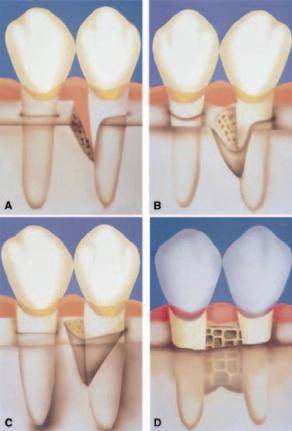

Number of bony walls housing the defect (Figure 1):

n one-wall;

n two-wall;

n three-wall; or,

n combinations.

Figure 1: Schematic diagram describing the number of walls in intrabony defects. A: one-wall intrabony defect; B: two-wall intrabony defect; C: three-wall intrabony defect; D: interproximal crater. (Figure reproduced with permission.)14